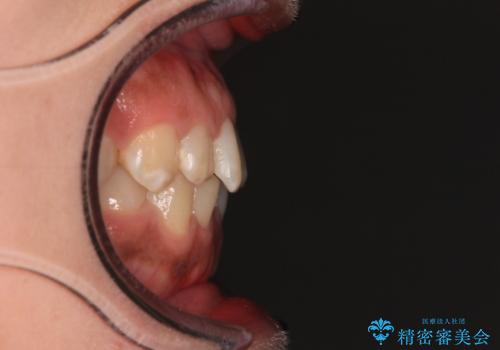

- 上下前歯の叢生を気にして来院された患者様です。

軽度な叢生であり、安価で短期間の治療を規模されていたため、インビザライン・モデレートを用いて矯正治療を行うこととしました。